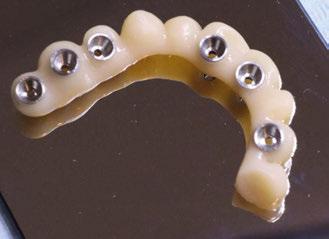

Presentamos el tratamiento rehabilitador de una paciente, realizado íntegramente en una sesión. Para este caso se ha utilizado un protocolo quirúrgico digital y guiado mediante la Plataforma de Planificación Bego Guide. Asimismo, se ha diseñado digitalmente una prótesis de carga inmediata atornillada e impresa con resina Bego VarseoSmile TriniQ®. Por lo tanto, se trata de un caso cuyo tratamiento precisa diferentes fases, pero efectuadas, todas ellas, el mismo día. De forma sencilla y cómoda para la paciente y el odontólogo, se ha obtenido una rehabilitación fija, funcional y estética. Palabras clave: Cirugía guiada, implantología oral guiada, cirugía sin colgajo, férula quirúrgica, rehabilitación fija maxilar, impresión digital, escáner intraoral, implantes dentales.

Figura 34. Rehabilitación superior impresa en resina Bego VarseoSmile TriniQ® lista para atornillar. Se han anulado de la oclusión aquellos implantes que no obtuvieron una estabilidad primaria superior a 35 N/cm2 Figura 31. Escaneado intraoral postcirugía. Figura 32. Rehabilitación recién impresa a través de impresora Varseo XS con resina Bego VarseoSmile TriniQ®. Figura 33. Ajuste pasivo entre aditamentos protésicos y la rehabilitación impresa.

Figura 35. Visión gingival de la rehabilitación impresa.

aproximadamente una hora y media. Usamos resina Bego VarseoSmile TriniQ® para puentes definitivos. Aunque en este caso la vamos a usar para confeccionar unas prótesis fijas atornilladas provisionales de larga duración, dado al aumento de dimensión vertical que vamos a realizar a la paciente, de esta forma obtendremos una neuroprogramación de la ATM reinstaurando una Dimensión Vertical apropiada y mejorando la estética facial de la paciente. Excluimos de la carga aquellos implantes que no obtuvieron una estabilidad primaria superior a 35 N/ cm2. El material permite la realización de una carga inmediata en material definitivo en puentes (Figuras 31 a 38).